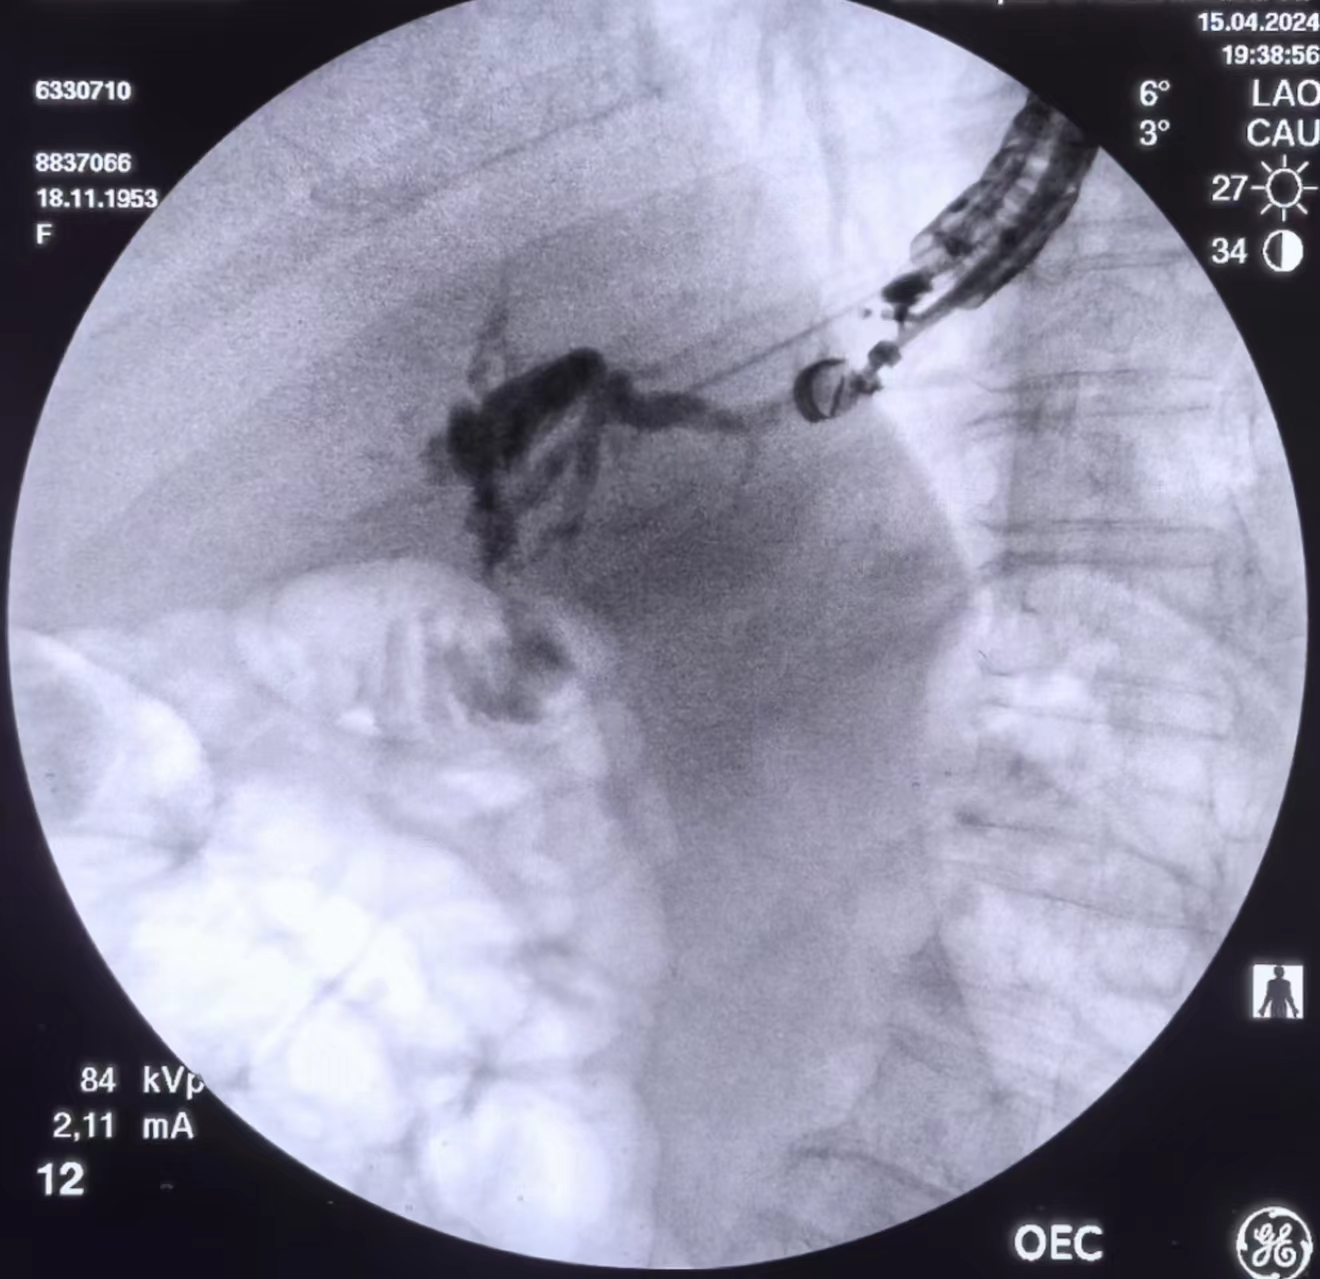

分享一例EUS-BD,向大家汇报一下

下图为患者部分手术图像

导丝不能通过胆肠吻合口,一直打圈

超选导丝到达肠腔